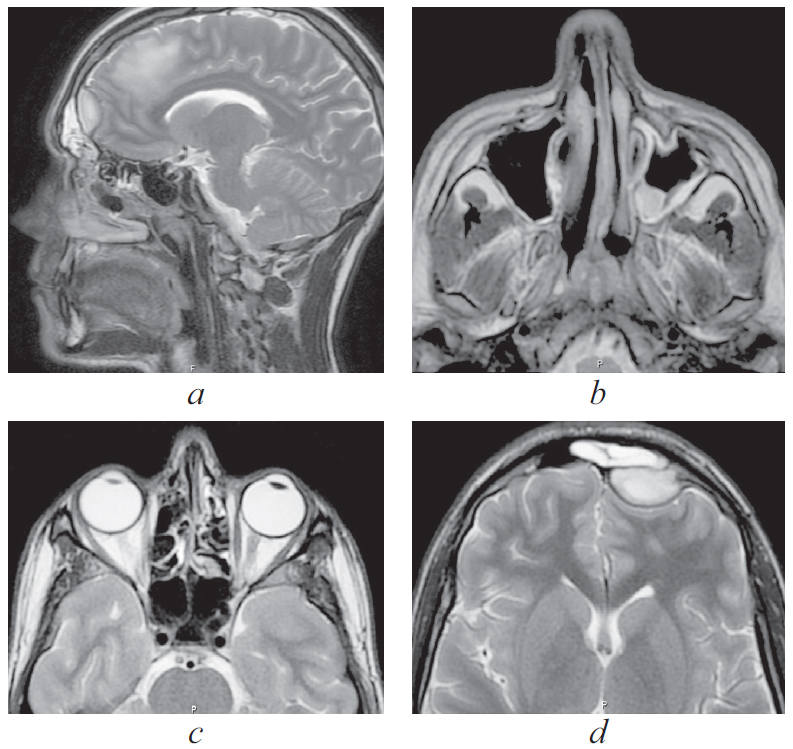

По результатам МРТ головного мозга от 16.06.2021 (рис. 2): МР-признаки подоболочечного скопления жидкости с высоким содержанием белка, воспалительных изменений оболочек в левой лобной области. Картина соответствует субдуральной эмпиеме.

Рис. 2. Магнитно-резонансная томография головного мозга от 16.06.2021: а — сагиттальная проекция в режиме Т2. Прослеживаются воспалительные изменения оболочек в левой лобной области. Картина соответствует субдуральной эмпиеме; b — аксиальная проекция в режиме Т2. Снижение пневматизации левой верхнечелюстной пазухи, пристеночный отек слизистой; c — аксиальная проекция в режиме Т2. Снижение пневматизации клеток решетчатого лабиринта; d — аксиальная проекция в режиме Т2. Воспалительные изменения оболочек в левой лобной области, субдуральная эмпиема

Fig. 2. Magnetic resonance imaging of the brain from 16.06.2021; a – sagittal projection in T2 mode. Inflammatory changes in the membranes in the left frontal region are traced. Picture consistent with subdural empyema; b – axial projection in T2 mode. Decreased pneumatization of the left maxillary sinus, parietal edema; c – axial projection in T2 mode. Decreased pneumatization of cells of the ethmoid labyrinth; d – axial projection in T2 mode. Inflammatory changes in the membranes in the left frontal region, subdural empyema

По результатам МСКТ ОНП от 16.06.2021: КТ-признаки синусита, осложненного эмпиемой левой лобной доли (рис. 3). В сравнении с данными МСКТ от 04.06.2021 отмечается положительная динамика в виде улучшения пневматизации левой лобной и верхнечелюстной пазух, а также клеток решетчатого лабиринта.

По результатам КТ ОНП от 08.11.2021: правосторонний сфеноидит с уровнем жидкости, левосторонний верхнечелюстной синусит с уровнем жидкости (рис. 4–6).

Рис. 4. Компьютерная томография околоносовых пазух и головного мозга от 08.11.2021: аксиальная проекция в режиме skull. Тотальное затенение правой половины пазухи клиновидной кости справа, уровень жидкости в левой верхнечелюстной пазухе

Fig. 4. Computed tomography of the paranasal sinuses and brain from 08.11.21: axial projection in skull mode. Total shading of the right half of the sphenoid sinus on the right, fluid level in the left maxillary sinus

Рис. 5. Магниторезонансная томография головы от 10.11.2021: правосторонний сфеноидит, тромбоз кавернозного синуса слева. Слева — коронарная проекция в режиме Т2. Тотальное затенение правой половины пазухи клиновидной кости, сужение кавернозного синуса слева; справа — аксиальная проекция в режиме Т2. Признаки тромбоза кавернозного синуса слева

Fig. 5. Magnetic resonance imaging of the head from 10.11.2021: right-sided sphenoiditis, thrombosis of the cavernous sinus on the left. Left: coronal projection in T2 mode. Total shading of the right half of the sphenoid sinus, narrowing of the cavernous sinus on the left; right: axial projection in T2 mode. Signs of thrombosis of the cavernous sinus on the left

Рис. 6. Магнитно-резонансная томограмма головного мозга. Признаки тромбоза кавернозного синуса. 1 — Венозный застой в ретробульбарной клетчатке; 2 — cужение просвета сифона внутренней сонной артерии слева; 3 — неоднородность структуры

Fig. 6. Signs of cavernous sinus thrombosis on magnetic resonance imaging of the brain. 1 — Venous congestion in the retrobulbar tissue; 2 — narrowing of the lumen of the siphon of the internal carotid artery on the left; 3 — structure heterogeneity